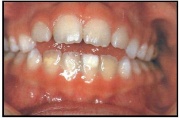

Valehambumus

Hammaste asendianomaaliad on tingitud tavaliselt arenguhäirest.